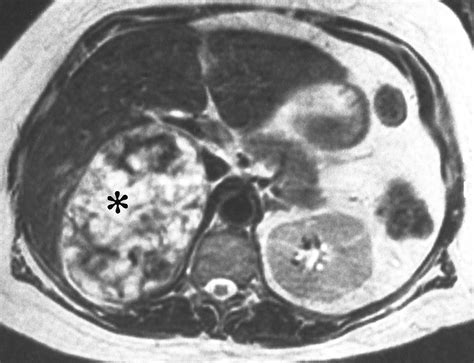

• Imaging tests: Computed tomography (CT) scans and magnetic resonance imaging (MRI) are commonly used to detect adrenal adenomas. These tests provide detailed images of the adrenal glands and can help determine the size and location of the tumor.